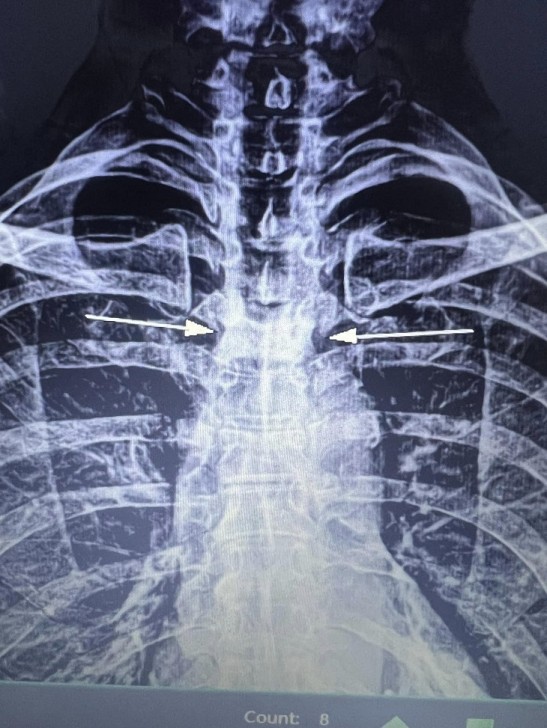

AFN.az xəbər verir ki, tanınmış həkim Aydın Əliyev bu sahədə vəziyyətin getdikcə ağırlaşdığını bildirib. O, xəstələrdən birinin müayinə nəticələrini paylaşaraq bunları yazıb: “Onkoloji xəstəliklərin müayinə və müalicəsinin hələ də icbari tibbi sığorta tərəfindən qarşılanmamasının daha bir qurbanı. Sağ qamış sümüyündəki törəmənin maddi imkansızlıq səbəbindən vaxtında və sistemli müalicə və ya əməliyyat edilməməsi səbəbindən fəqərələrə, qabırğalara, kürək, çanaq sümüklərinə, ağciyərə çoxsaylı metastazları. Demək olar ki, adam həyatını itirib”.